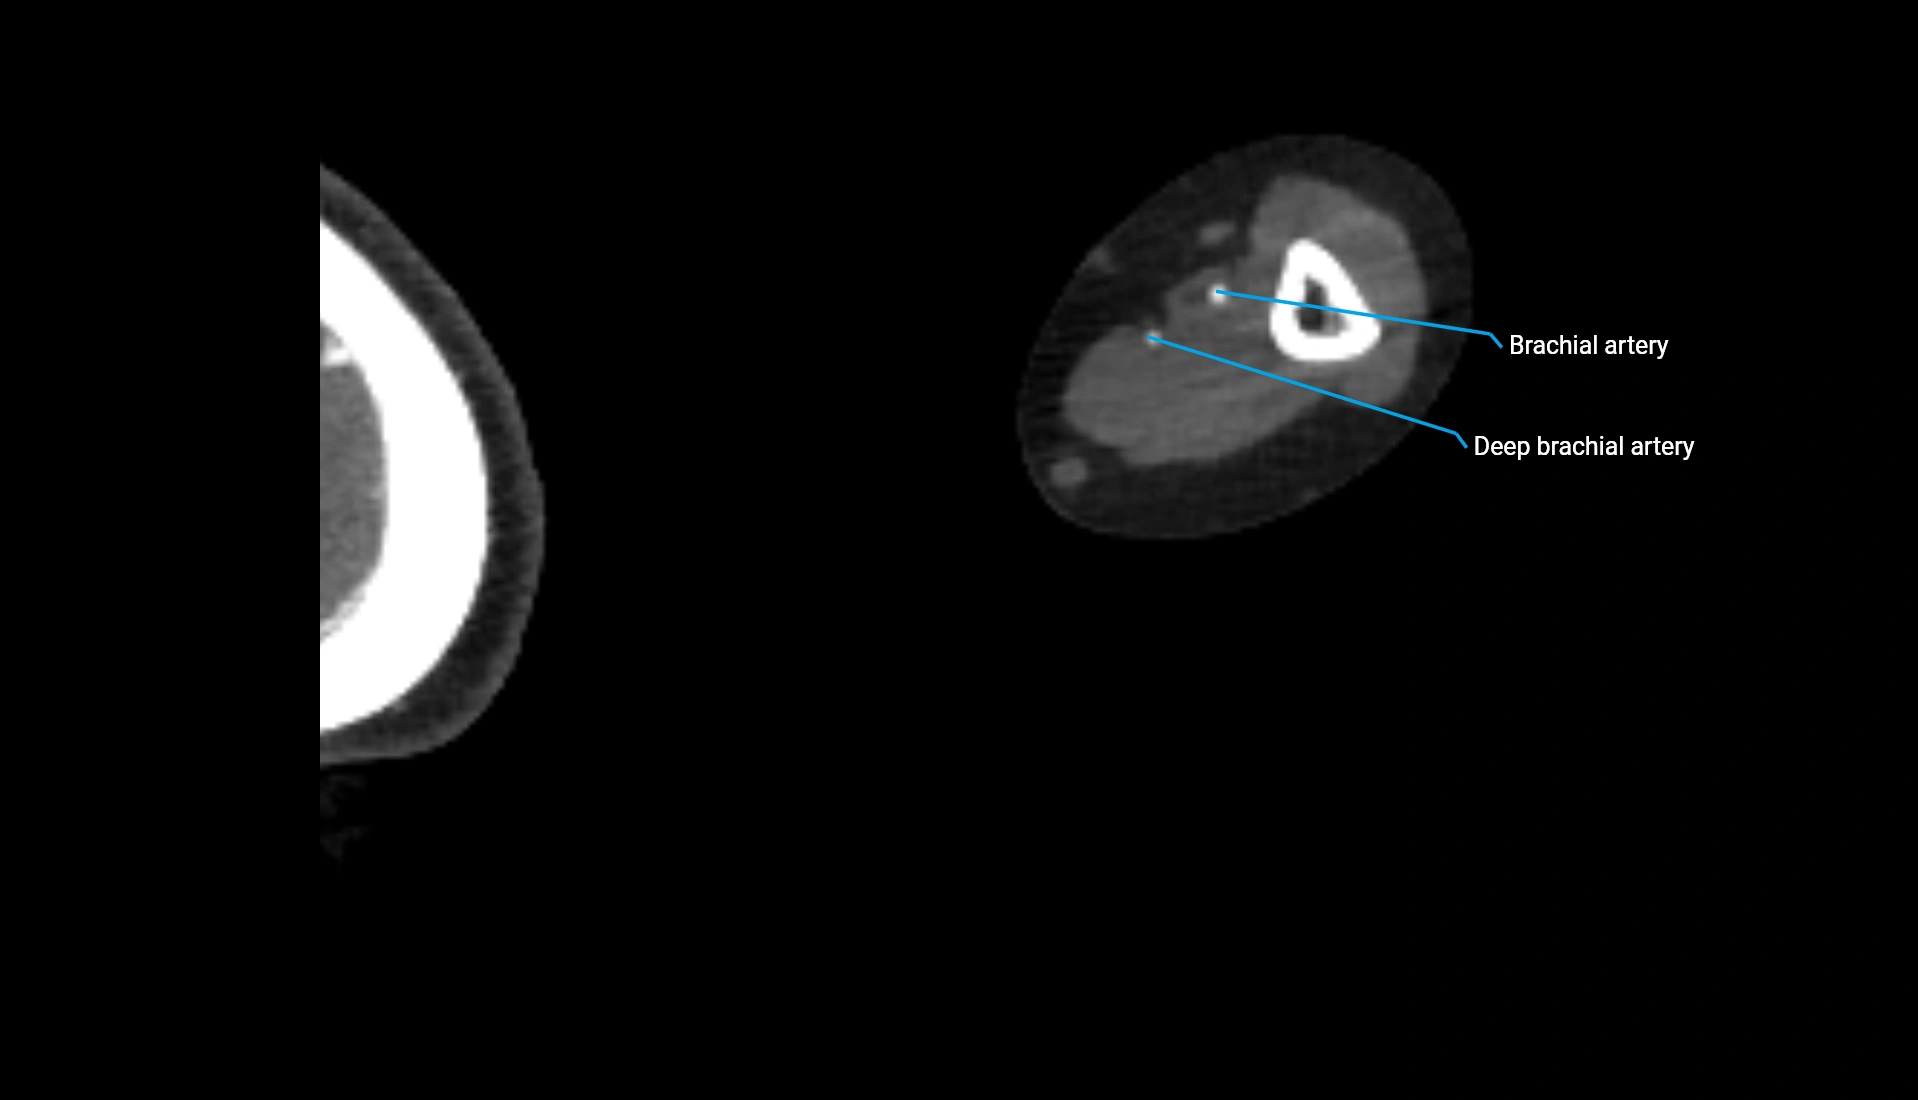

CT Appearance

Non-Contrast CT:

• Cortex: High-density, sharply defined

• Subchondral bone: Dense cancellous matrix

• Articular surface: Smooth concave contour articulating with the capitellum

• Excellent for evaluating bone integrity, alignment, and subtle fractures